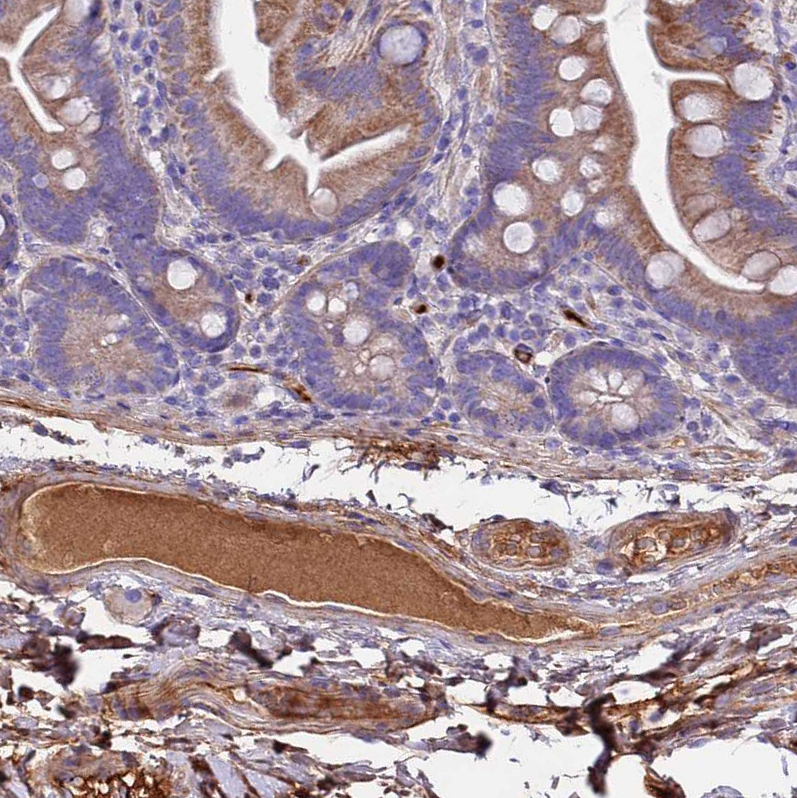

Immunohistochemical staining of human testis shows strong positivity in secretion.